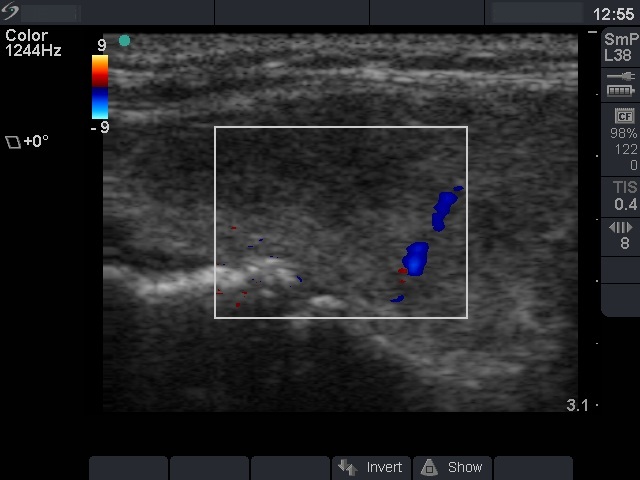

Ultrasonography: the right thyroid was echonormal with several hypoechogenic areas with blurred borders. The hypoechogenic areas were avascular. The left thyroid was hypoechogenic.